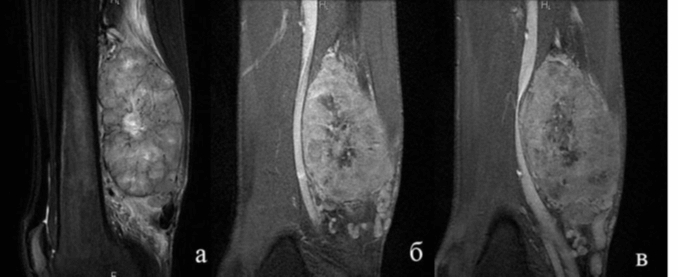

- магнитно-резонансная и компьютерная томография;

МРТ и КТ помогают установить размеры опухоли, ее расположение и наличие метастазов. УЗИ позволяет оценить внутреннюю структуру новообразования и выявить мутированные клетки в мягких тканях. Рентгенография показывает изменения в костях и хрящах. Для повышения информативности рентгеновских снимков иногда используют контрастные вещества (ангиография). Разнообразные методы исследования материала помогают определить стадию заболевания, наличие метастазов, подтвердить или опровергнуть диагноз и отслеживать динамику патологии.

Комплексная диагностика позволяет собрать полную информацию о местоположении саркомы, ее размерах, консистенции, наличии метастазов и их кровоснабжении, а также о готовности клеток к делению.